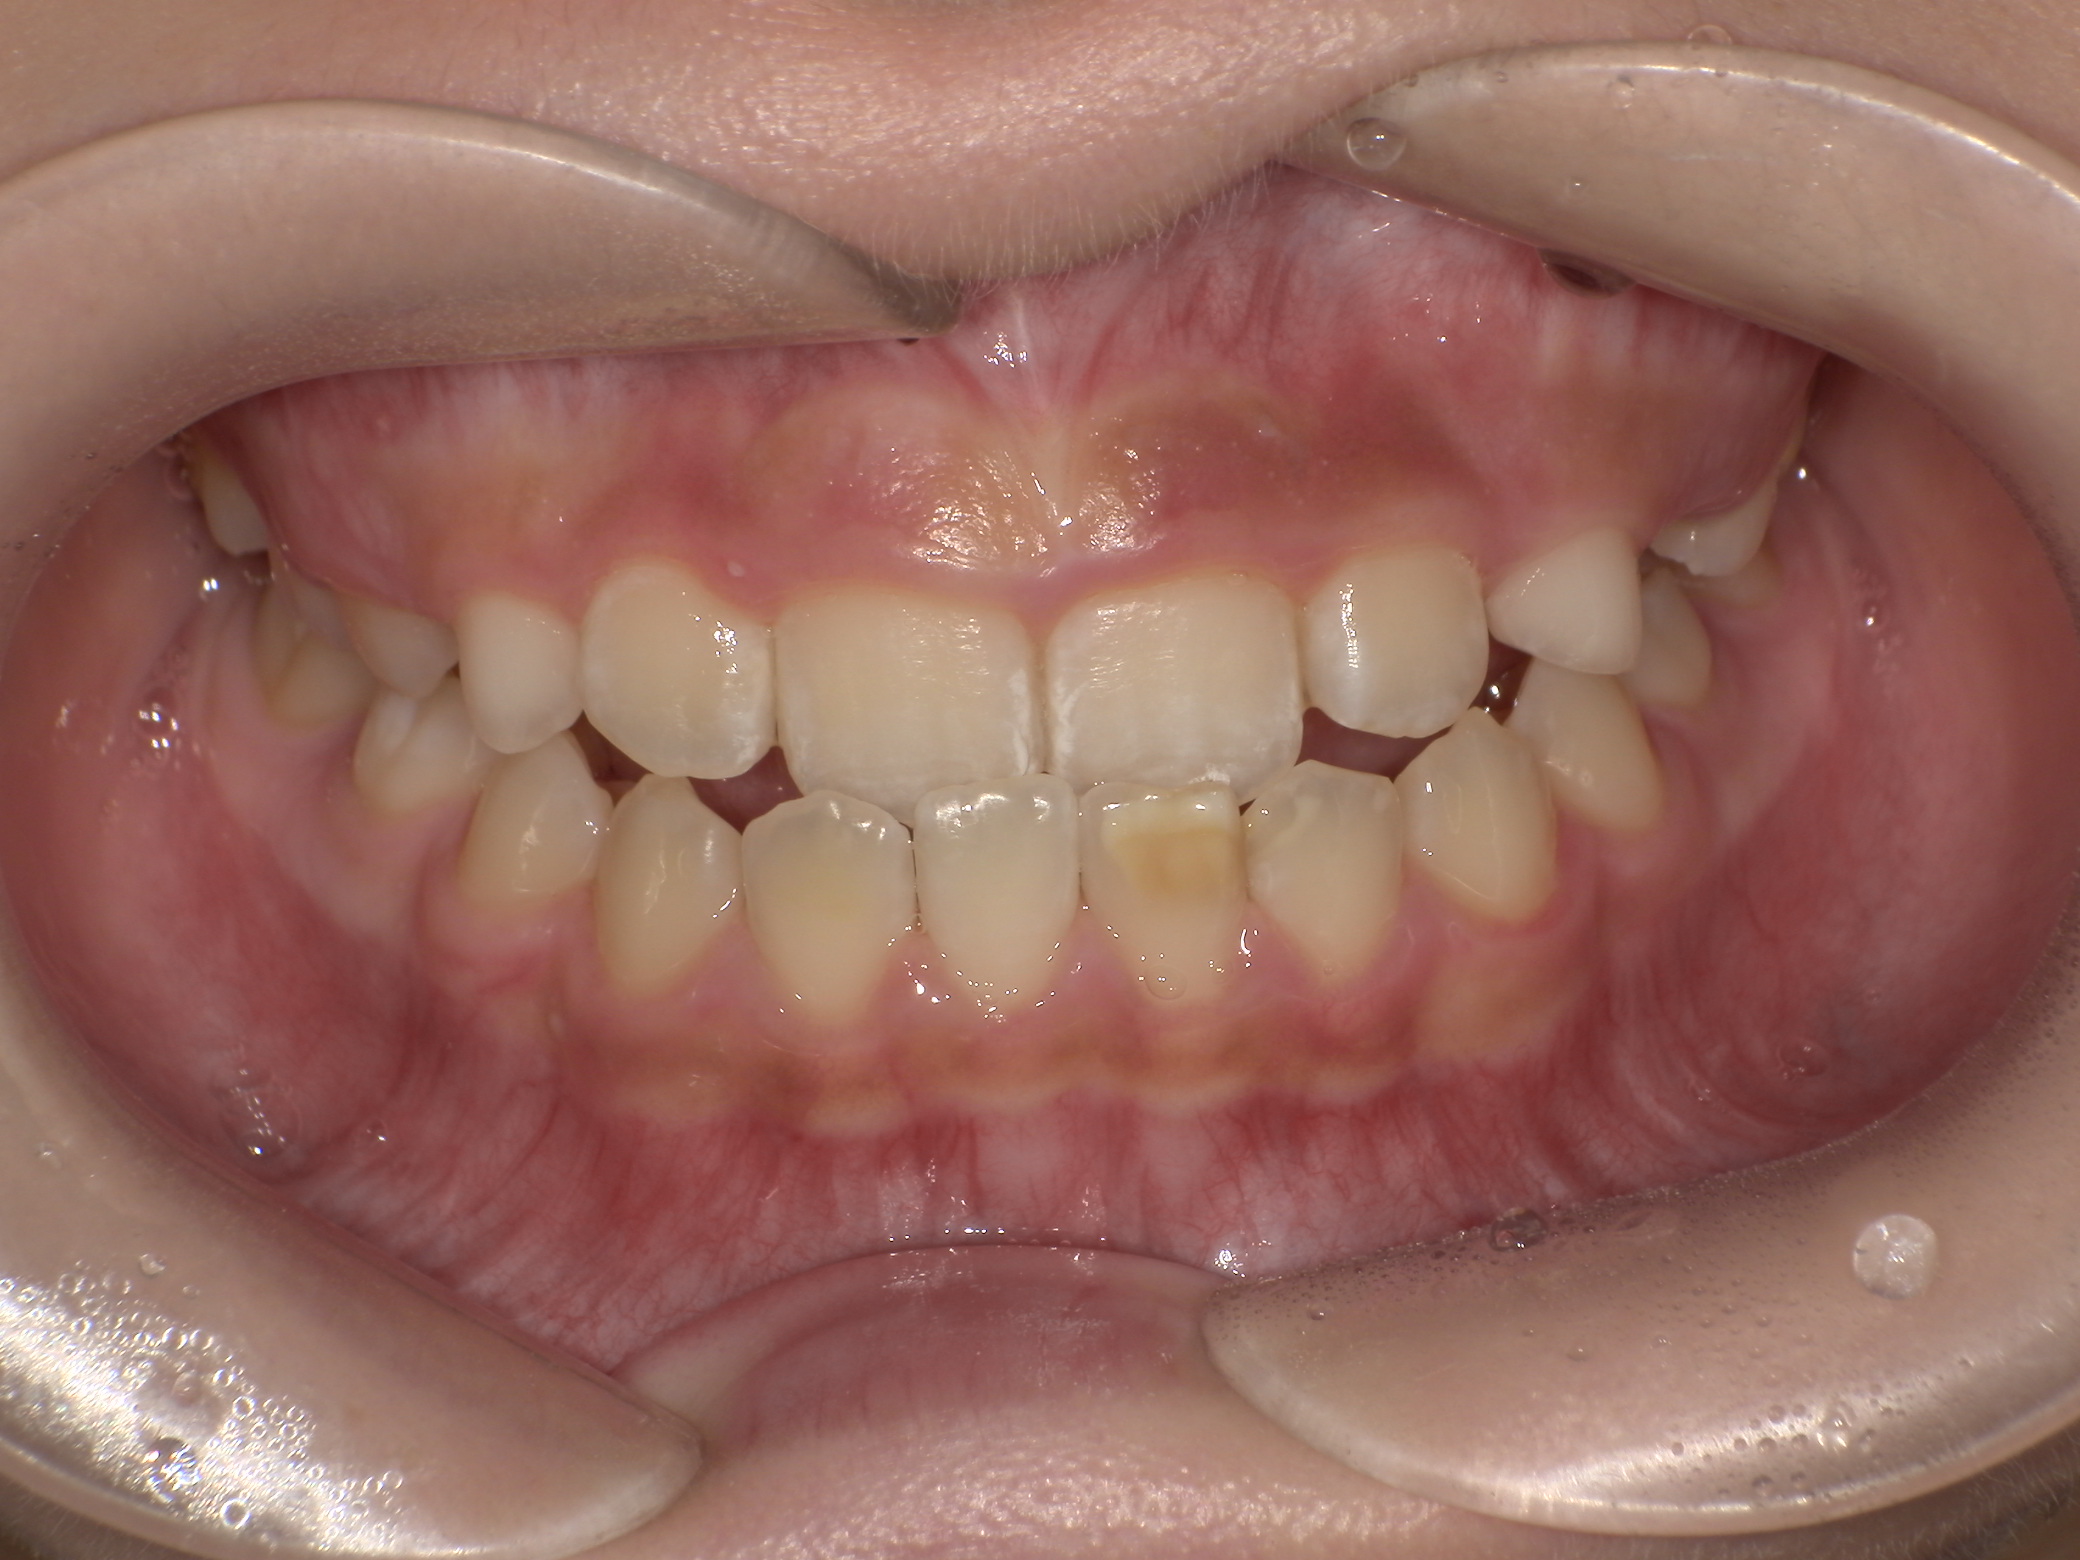

プレオルソ症例|下の前歯が出ているのが気になる

2026/03/24 小児矯正